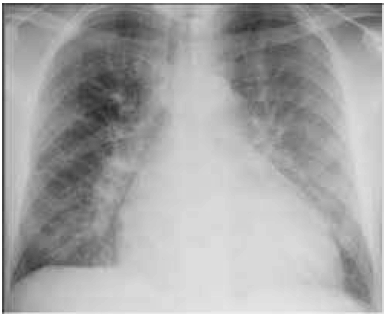

Paciente MDH, homem, de 42 anos de idade, foi internado por dispneia aos esforços há cinco meses, com sensação de opressão no tórax há uma semana. Nega tosse, expectoração ou chiado. Nega tabagismo. Seu exame físico da entrada revelou o seguinte: PA de 110 mmHg × 76 mmHg; FC de 54 bpm; saturação de O2 (ar ambiente) de 91%. Ausculta cardíaca: hiperfonese e desdobramento de segunda bulha em foco pulmonar. Turgência jugular bilateral. Pulmões com estertores bibasais. Apresenta ecocardiograma transtorácico com FEVE de 34% e a radiografia inicial mostrada a seguir. O paciente é estabilizado no terceiro dia da internação e já está com a volemia estável.

A partir desse caso hipotético, assinale a alternativa correta, a respeito do planejamento pós-alta desse paciente, de acordo com a Diretriz Brasileira de Insuficiência Cardíaca Crônica e Aguda.